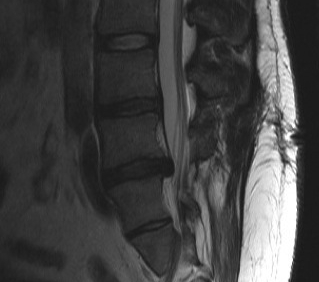

MRI

T2 Sagittal - myelogram

T1 Axial - see nerve root against white fat

MRI changes

1. Central root clumping

2. Empty sac appearance

3. Soft tissue mass in subarachnoid space